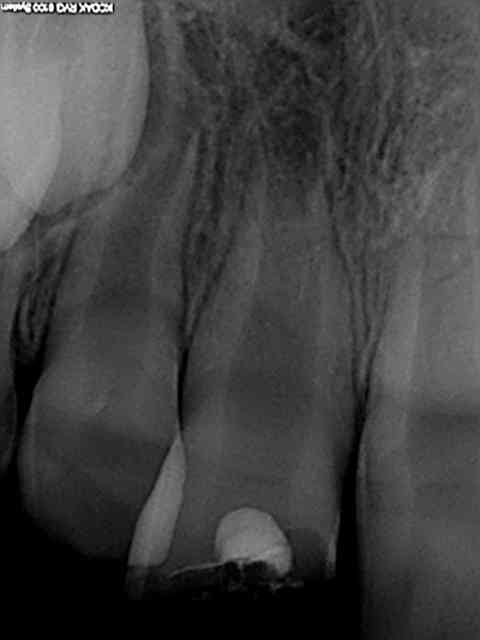

Cas concret, patient 8 ans fracture de la 11 avec effraction pulpaire. Traitement mta dans la chambre collage du morceau cassé et oh! miracle 8 mois après pont dentinaire et apexogenèse en branle. Cout 120 euros le sachet de mta. La sécu rembourse une pulpo à 16.87 euros juste de quoi mettre un eugenate et de découvrir l'apex béant avec en plus une bonne pèche 6 mois plus tard et dent nase. Les parents du patient vont témoigner sur lcp que les dépassements d'honoraires sont une honte ? Quel pays lamentable.

Bravo mais là, j'aurai mis du HN pour facturer le MTA.

Que je sache, l'apexogénèse n'est pas dans la NGAP.